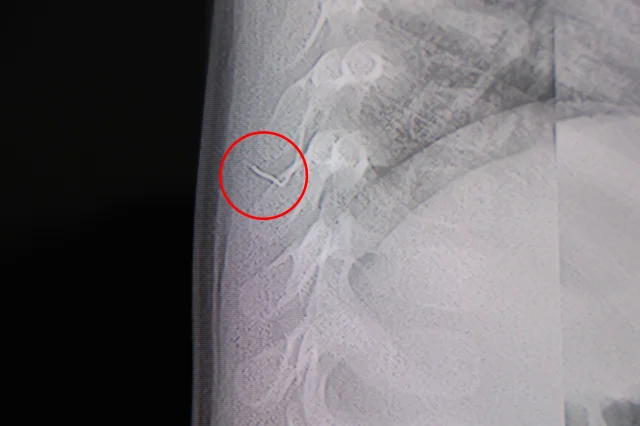

Ailenin son olarak başvurduğu hastanede yapılan tetkiklerde, yabancı cismin cilt altında, omurilik kanalına yakın bir bölgede olduğu ve akciğer zarına doğru ilerlediği belirlendi. Hasta, genel anesteziye alınmadan, lokal anestezi ve sedasyon eşliğinde ameliyata alındı. Yapılan müdahalede yabancı cisim tamamen çıkarıldı. Çıkarılan cismin ince zımba teline benzer metal bir tel olduğu ve yaklaşık 2 santimetre uzunluğunda bulunduğu tespit edildi. Hasta aynı gün taburcu edildi.

Konuya ilişkin açıklama yapan Beyin ve Sinir Cerrahisi Uzmanı Prof. Dr. İdris Altun, “Sırtında yabancı bir cisim olduğu söylenmiş ancak çıkarılamayacağı ve 8 yaşına kadar beklenmesi gerektiği ifade edilmişti. Bize başvurduğunda yaptığımız tetkiklerde, cilt altında, omurilik kanalına çok yakın ve akciğer zarına doğru ilerleyen bir yabancı cisim tespit ettik. Hastamızı tamamen uyutmadan, lokal anestezi ve sedasyon eşliğinde müdahale ederek lezyonu tamamen çıkardık. Çıkardığımız cismin ince zımba teline benzer, yaklaşık 2 santimetre uzunluğunda metal bir tel olduğunu gördük. Bu yabancı cisim alınmasaydı bölgede enfeksiyon gelişebilirdi. Enfeksiyon sonucu omurilik kanalında ciddi hasarlar oluşabilir, çocuk büyüdükçe cismin hareket etmesine bağlı olarak omurilikte zedelenmeler meydana gelebilirdi. Ayrıca yana doğru ilerleyerek akciğer zarına ve akciğere batma riski vardı. Bu da enfeksiyona ve ilerleyen süreçte tümörle karışabilecek tablolara neden olabilirdi. Şu an hastamız gayet sağlıklı. Gerekli kontrolleri yaptık ve aynı gün taburcu ettik” dedi.